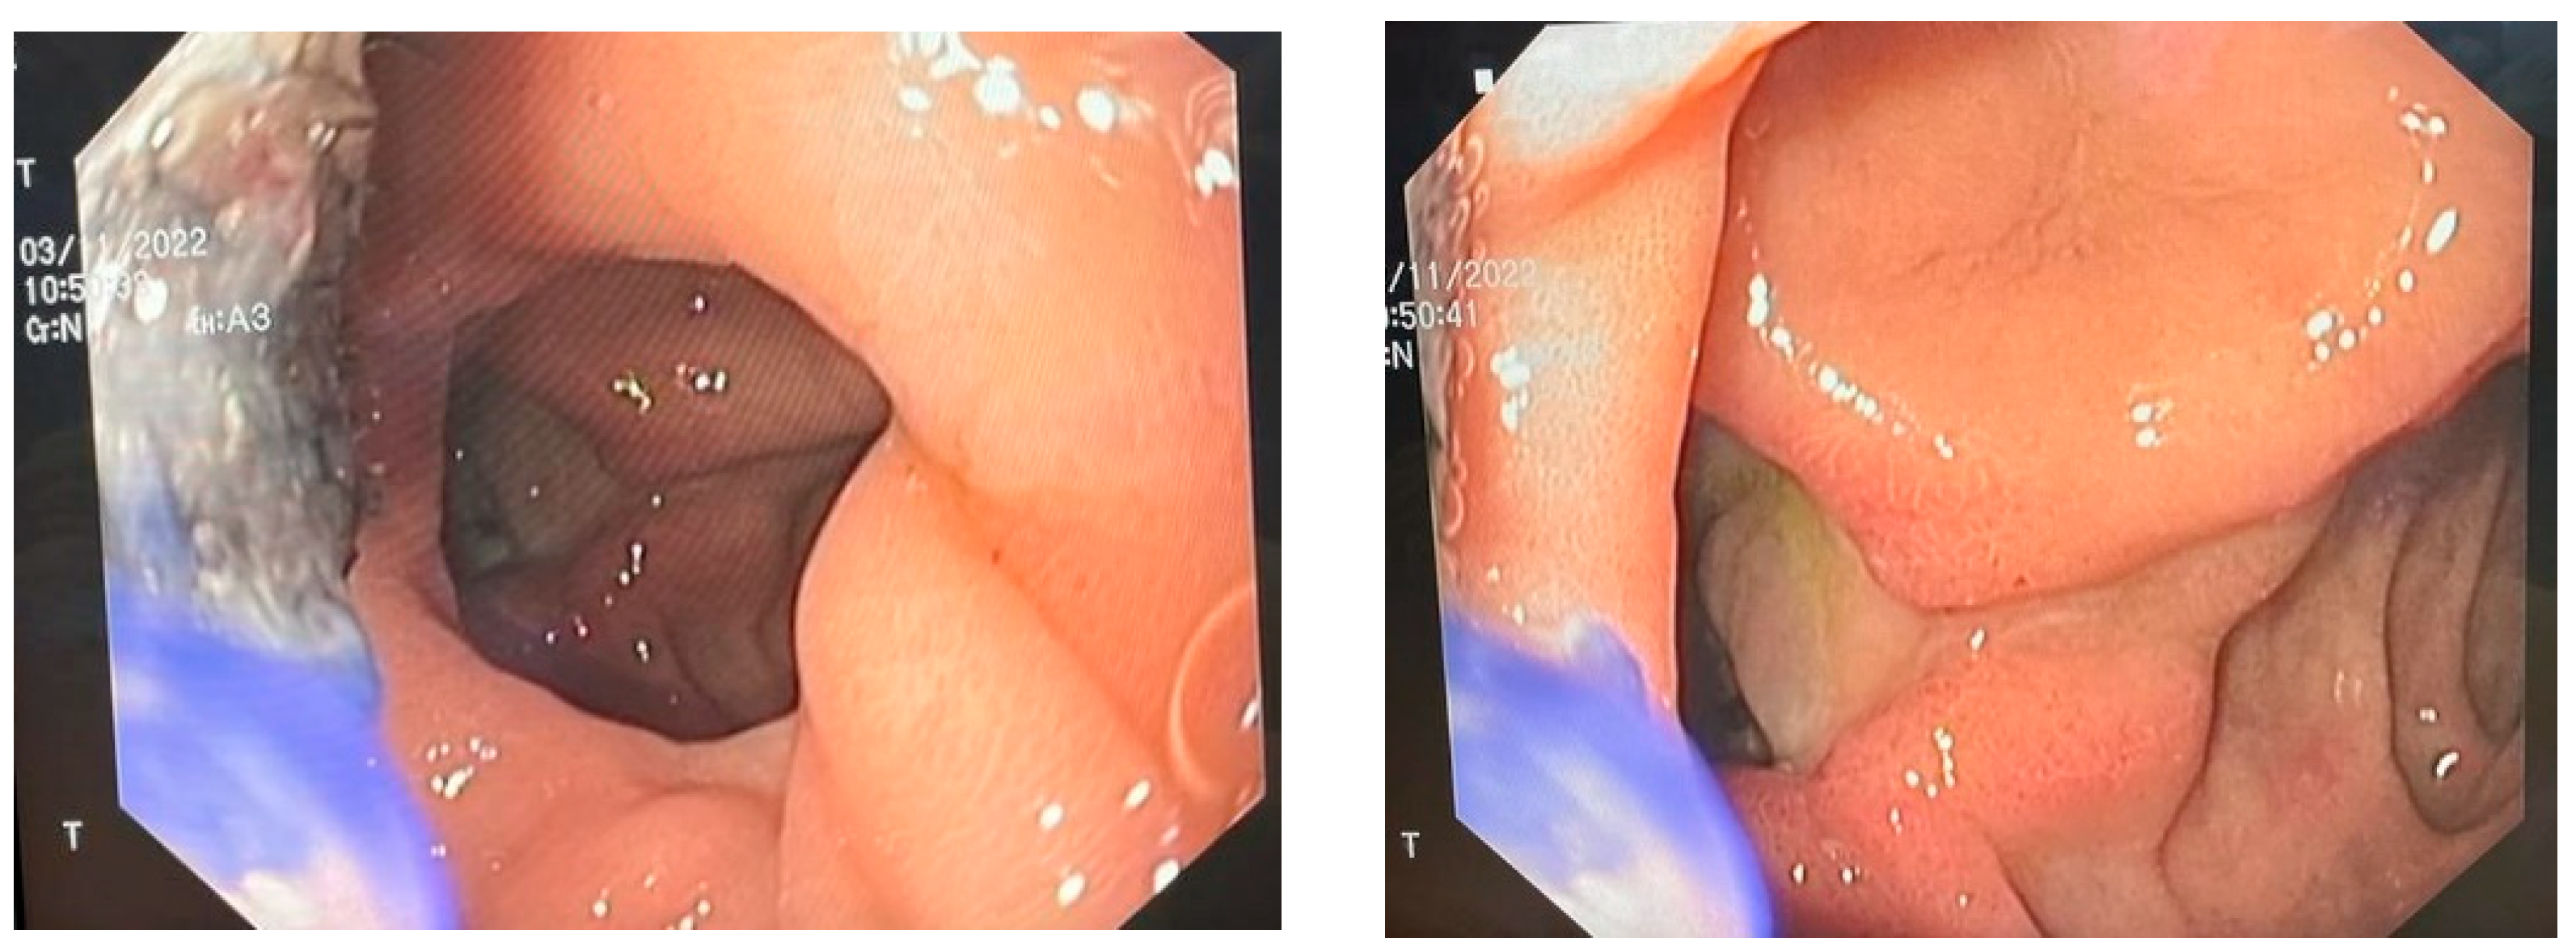

Surgical intervention was decided as the therapy. Upon exploratory laparotomy, we revealed the presence of an advanced adhesion process with a mass formation. This mass was found to be compressing the duodenum and pancreas but was not obstructing the GI tract. Once viscerolysis was performed, the presence of a subphrenic abscess located bilaterally containing purulent, aero-digestive content was confirmed. The evacuation of the abscess was performed via the application of three rubber drainage tubes. Because of the important inflammatory status and the high grade of adhesions, the perforation could not be objectified. An endoscopic evaluation was performed, and we found a duodenal defect in segment I, which was communicating with the residual cavity of the abscess (Figure 1).

Figure 1.

Endoscopic view of the duodenal ulcer.